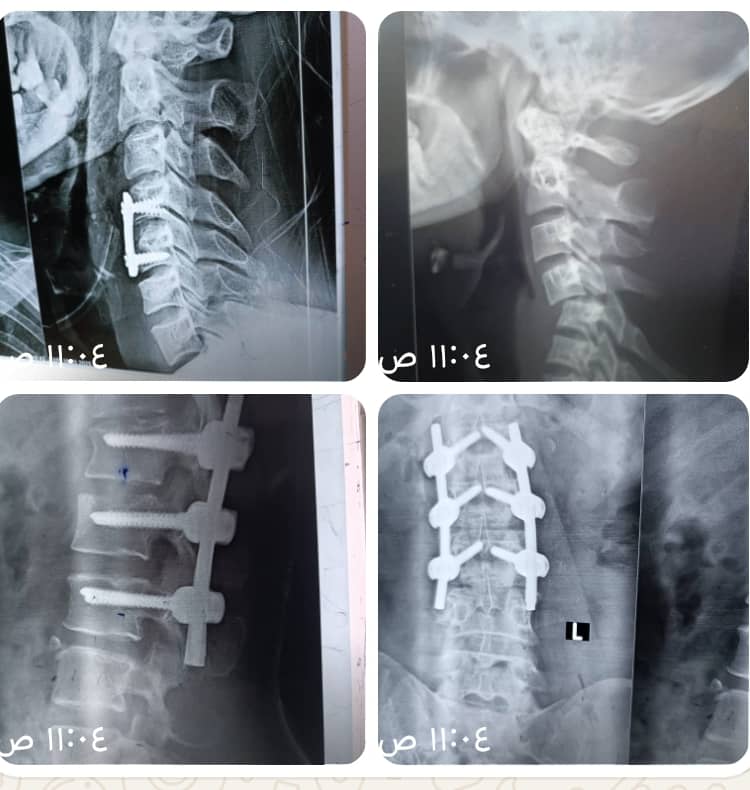

ثم بجهود فريقنا الطبي المتميز، وبجهود طاقم العمليات المتميز تم بحمد الله إجراء عملية تثبيت رقبة امامية.

عملية جراحية تم إجراؤها بغرفة عمليات العظام بقسم العمليات الكبرى أجراها استشاري_ العظام والعمود الفقري والأعصاب.